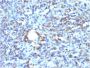

CD68 (Macrophage Marker)(rLAMP4/824), 0.2mg/mL

This antibody recognizes a glycoprotein of 110 kDa, which is identified as CD68. It is important for identifying macrophages in tissue sections. It stains macrophages in a wide variety of human tissues, including Kupffer cells and macrophages in the red pulp of the spleen, in lamina propria of the gut, in lung alveoli, and in bone marrow. It reacts with myeloid precursors and peripheral blood granulocytes. It also reacts with plasmacytoid T cells, which are supposed to be of monocyte/macrophage origin. It shows strong granular cytoplasmic staining of chronic and acute myeloid leukemia and also reacts with rare cases of true histiocytic neoplasia. Lymphomas are negative or show few granules. Primary antibodies are available purified, or with a selection of fluorescent CF® Dyes and other labels. CF® Dyes offer exceptional brightness and photostability. Note: Conjugates of blue fluorescent dyes like CF®405S and CF®405M are not recommended for detecting low abundance targets, because blue dyes have lower fluorescence and can give higher non-specific background than other dye colors.

Positive Control

IF (verified), IHC, FFPE (verified), WB (verified)